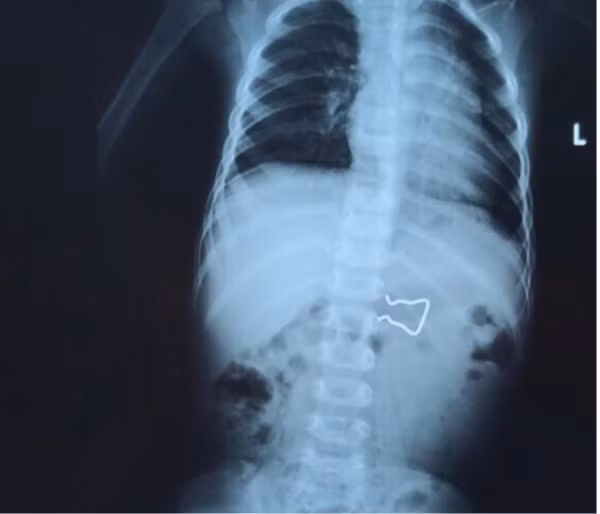

Mới đây, Bệnh viện Nhi đồng 2 (TPHCM) tiếp nhận bệnh nhi N.B.N.K (18 tháng tuổi) được Bệnh viện Đa khoa tỉnh Đắc Lắk chuyển lên vì nuốt phải dị vật là một cọng sắt sắc nhọn. Bệnh nhi không ói, không đau bụng.

Qua Xquang, các bác sĩ ghi nhận dị vật có hình dạng giống với vật dùng để cố định trong kẹp quần áo. Nhiều khả năng, nó bị rơi ra và bé đã nhặt chơi rồi vô tình nuốt phải.

BS CKII Nguyễn Minh Ngọc - Trưởng khoa Tiêu hóa - cho biết: Đây là một trường hợp khó vì hình dáng dị vật có hai cạnh sắc nhọn với kích thước lớn, khi gắp dị vật có thể gây tổn thương nhiều hơn niêm mạc đường tiêu hóa. Đặc biệt, dị vật cần được gắp ra nhanh chóng bởi nếu nó di chuyển vào sâu hơn sẽ gây biến chứng thủng ruột.